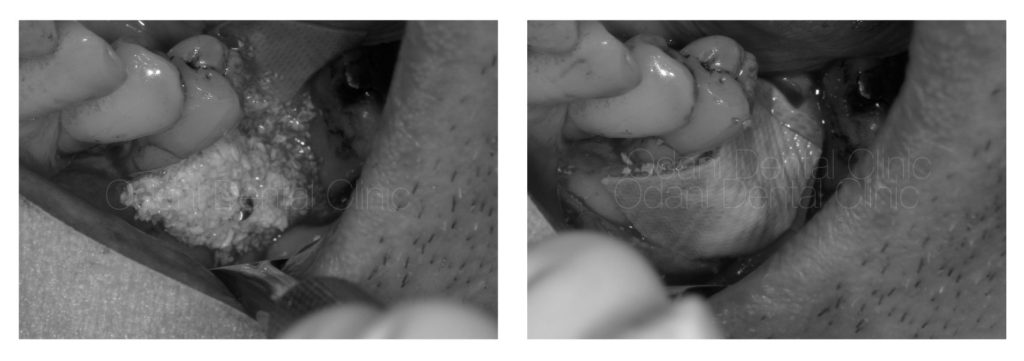

インプラントを埋め込むための骨造成

写真の患者様はもともと大きく骨が不足していたため、インプラントを埋め込めない状態でした。まずは骨を作ってから骨が固まるのを待って改めてインプラント埋入を行うこととしました。一番奥の歯も予後不良でありましたが、この骨造成のためには一時的に保存した方が骨が作りやすいと判断し一旦は保存しております。